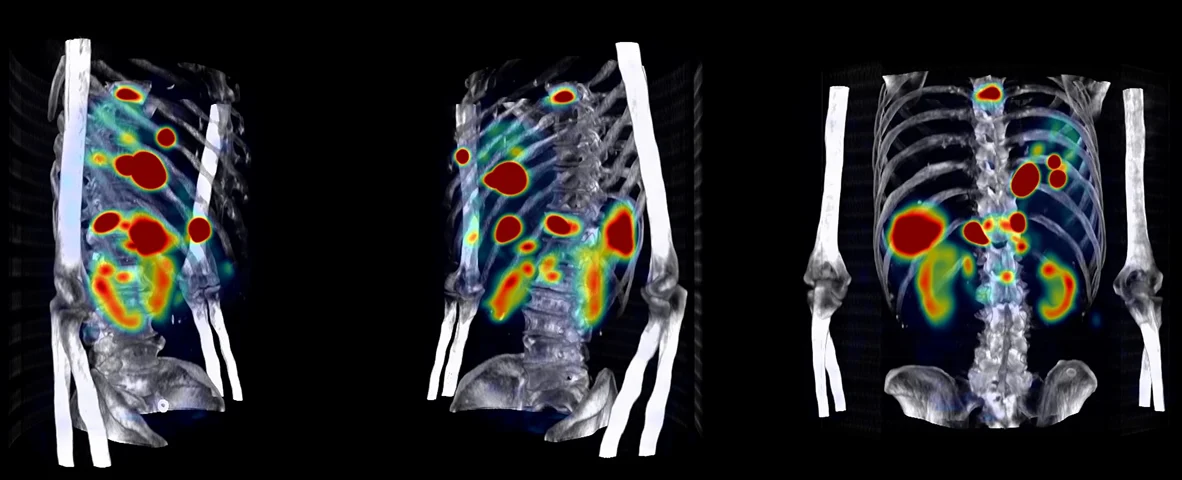

Medical imaging is one of the most data-intensive areas in oncology AI.

To enable AI models to interpret these images accurately, they must be annotated with extreme precision.

This is where medical image annotation for AI becomes essential.

High-quality medical image annotation ensures AI systems learn clinically relevant features rather than noise.

Through detailed and structured annotation processes, Pareidolia empowers AI models in:

High-quality annotation also helps AI development teams better interpret model outputs, enabling clearer visualization of detected regions and improving collaboration between data scientists and clinical experts.